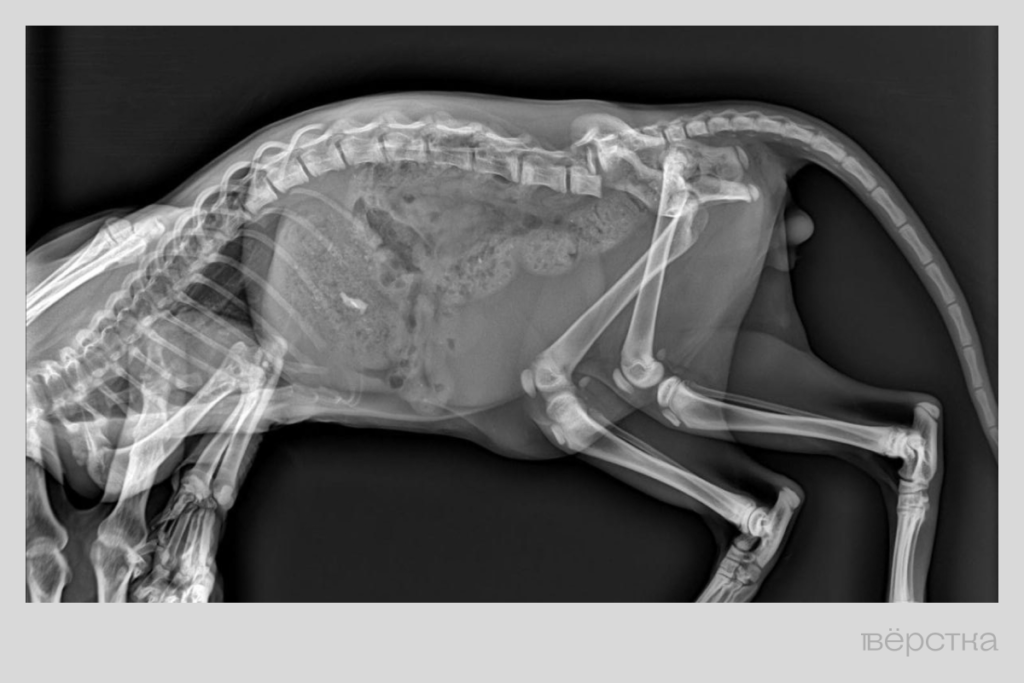

«Мы с соседкой вытащили его, а он хромат. Отвезли на рентген — оказалось, у него перелом позвоночника, — рассказывает Татьяна. — Местный хирург посмотрел на снимок и сразу сказал, что любые меры будут бесполезны».

Тогда снимок показали врачу из Москву. Сначала он ответил: «Тут ничего не сделаешь», но потом посмотрел на котёнка по видео и согласился попробовать помочь: увидел, что тот всё-таки ходит, хотя и подворачивает задние лапы, и хвост шевелится.